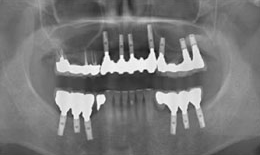

インプラント症例(1)30代 女性

治療後

上顎

保存困難な歯を抜歯後、インプラントを7本埋め込み、セラミックスクラウンを被せた

下顎

保存困難な歯を抜歯後、インプラントを6本埋め込み、セラミックスクラウンを被せた

インプラント

フィクスチャー13本

285,000×13=3,705,000円(税抜)

上部構造

(メタルボンドクラウン)18本

155,000×18=2,790,000円(税抜)

右上

メタルボンドブリッジ

90,000×4=360,000円(税抜)